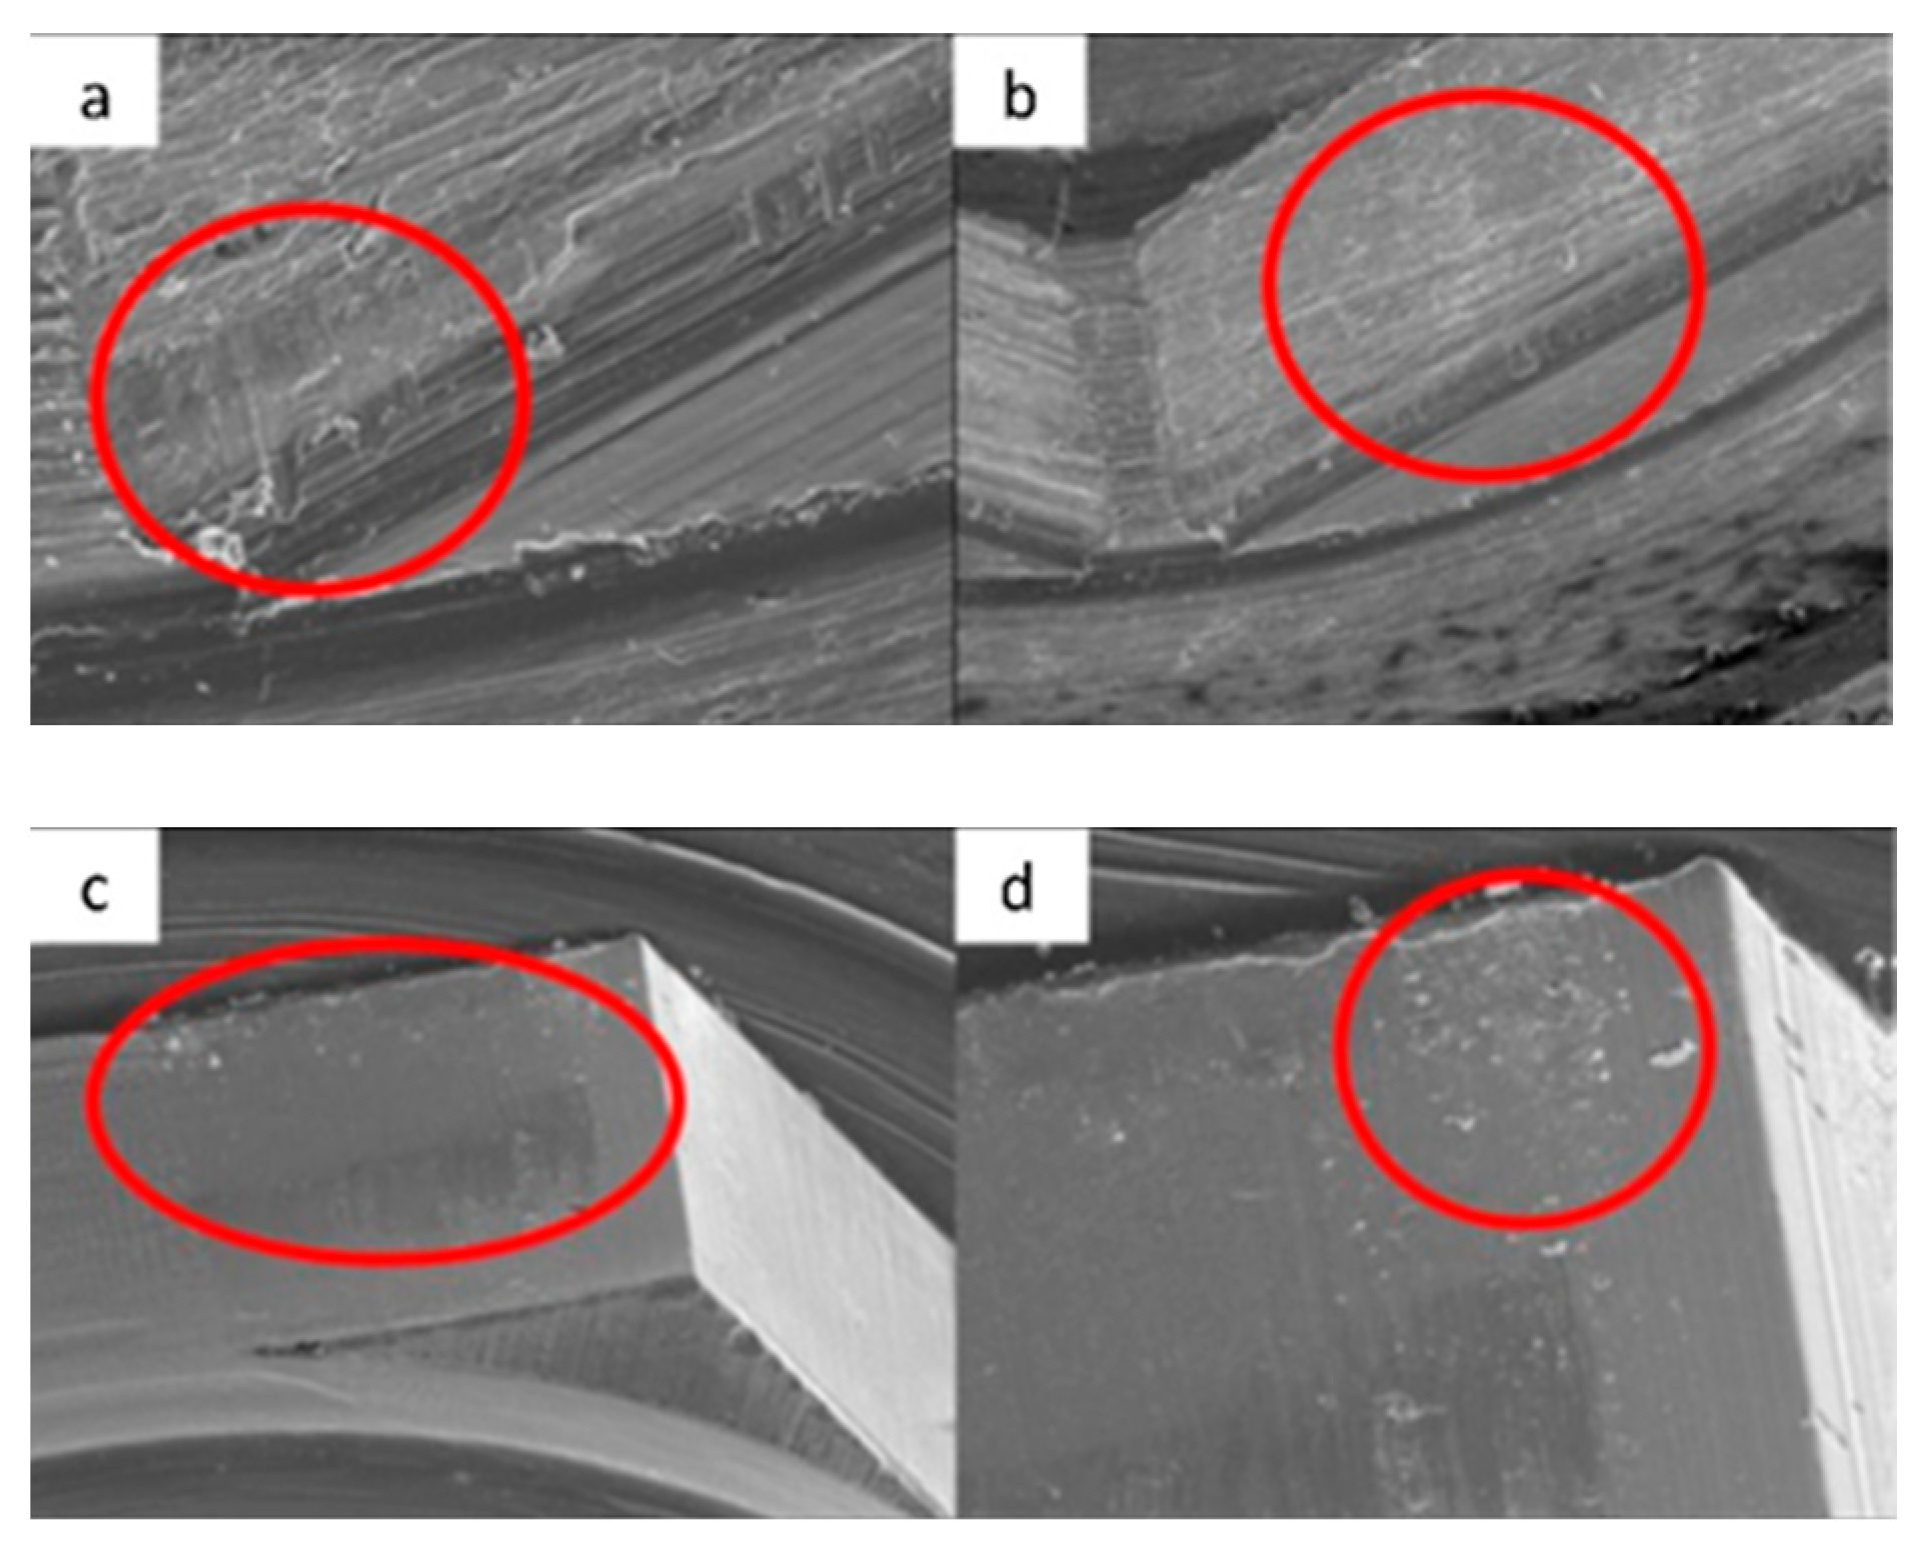

3.1. SEM

3.1.1. KL Implants

3.1.2. Essential Implants

3.1.3. SK2 Implants

3.1.4. Vega Implants

4.1. SEM Evaluation